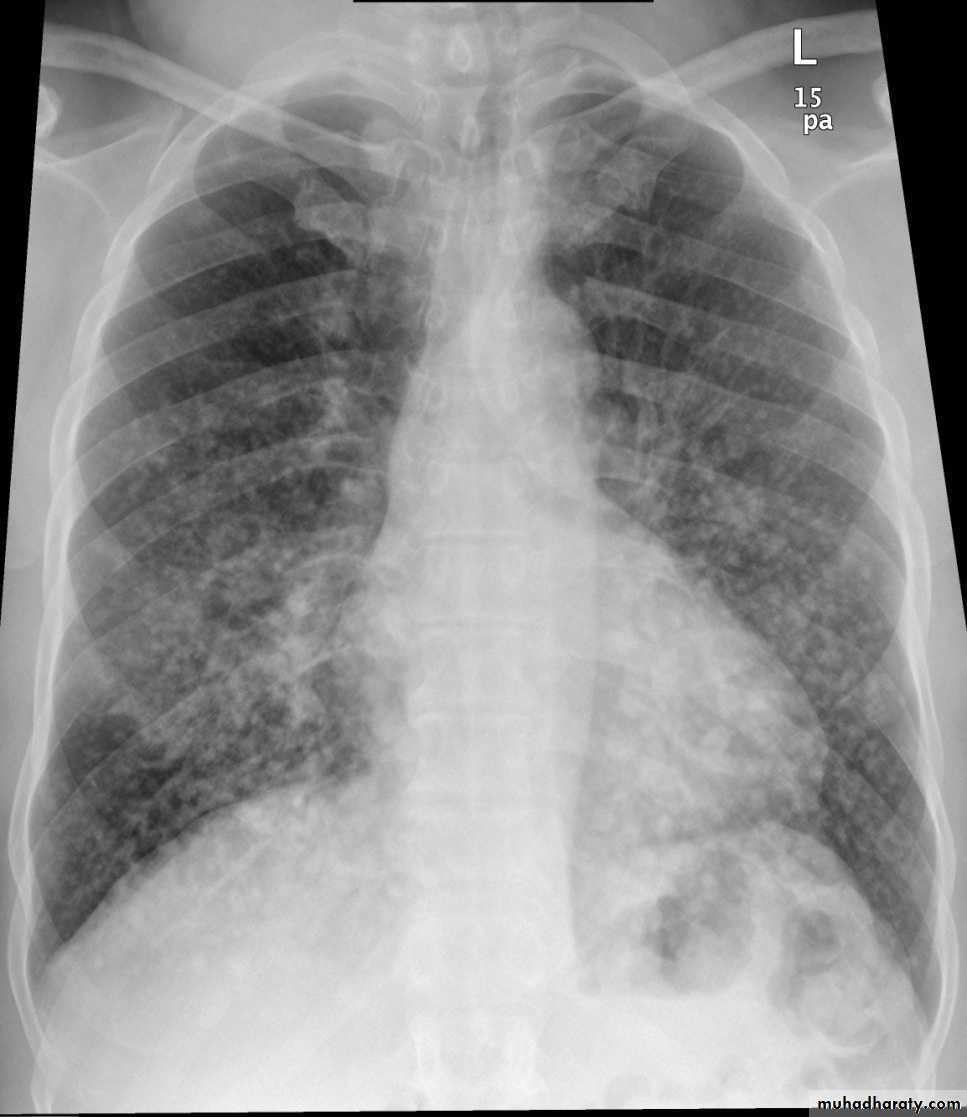

Pulmonary metastases are common and the result of metastatic spread to the lungs from a variety of tumors and can spread via blood or lymphatics.1.Cannonball metastases refer to large well circumscribed, round multiple opacities like cannonballs

3.innumerable small metastases (miliary pattern).